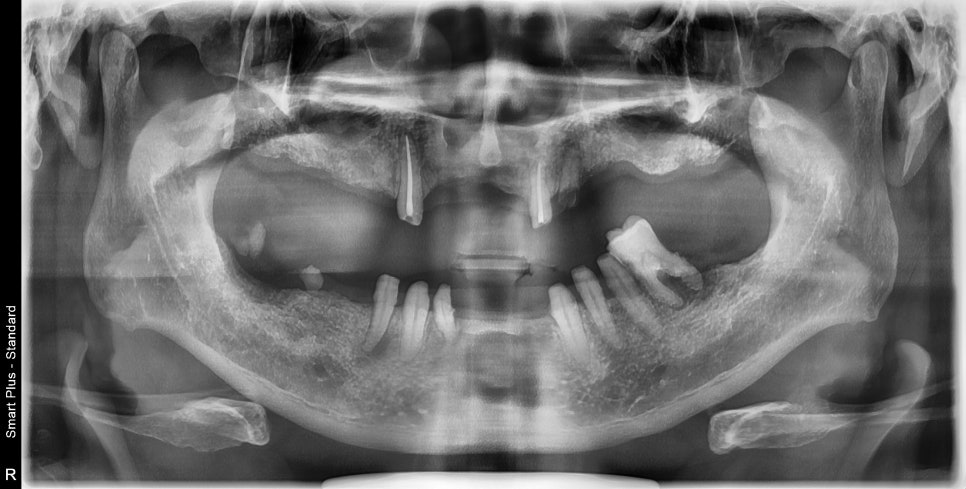

치아가 없으면 얼굴에도 변형이 올수 있습니다. 이번에 보여드릴 환자분은 어금니가 전부 없어진지 오래 되시고 앞니로만 식사를 하시던 분이었습니다. 어금니가 없어지게 되면 볼이 홀쭉해지고 위아래로도 높이가 낮아져 얼굴이 짧아져 보입니다. 전체 케이스를 다 하는데 8개월 가량 소요되었으며 지금은 만족스럽게 식사를 하고 계시...

치아가 없으면 얼굴에도 변형이 올수 있습니다.

이번에 보여드릴 환자분은 어금니가 전부 없어진지 오래 되시고

앞니로만 식사를 하시던 분이었습니다.

어금니가 없어지게 되면 볼이 홀쭉해지고 위아래로도 높이가 낮아져 얼굴이 짧아져 보입니다.

전체 케이스를 다 하는데 8개월 가량 소요되었으며

지금은 만족스럽게 식사를 하고 계시다고 합니다.